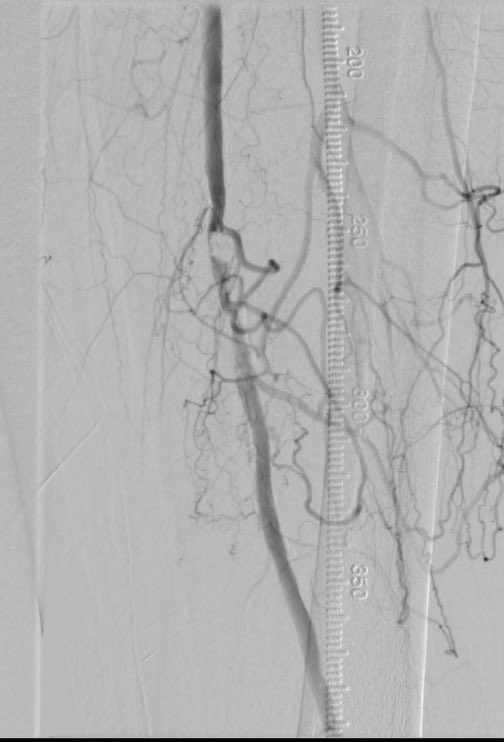

Understanding the pedal arch course crucial to successful arch intervention and for retrograde treatment of tibial disease. Rotation from ipsilateral cranial view to the contralateral oblique view shown here #SCAIPAD #CLI @FadiSaab17 @SOBE_Vascular @shishem @DrAmirKaki @DanHan